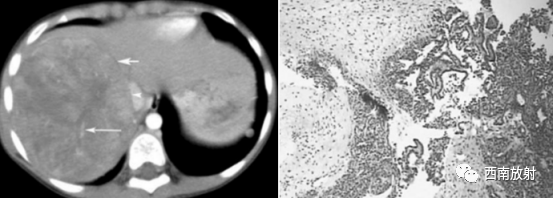

▲病例4:胎儿型肝母细胞瘤:男,9个月,肝右叶肝母细胞瘤,CT增强扫描示肿 瘤与周围正常肝组织边界清楚,似有假包膜 (短箭头),其内有裂隙状低密度区,瘤内可见较多粗细不一的肿瘤血管 (长箭头),下腔静脉主要为受压改变 (箭头 )。病理为肝母细胞瘤,胎儿型。

HE染色,低倍 40.肿瘤细胞排列成不规则梁索状,瘤细胞呈小圆形,胞浆丰富,部分透亮,胞核圆形或卵圆形,单个核仁,核分裂少见。肿瘤细胞间质血窦丰富,可有髓外造血灶瘤。另外见凝固性坏死,穿剌组织中未见间叶分化的成份,符合肝母细胞瘤,胎儿型。